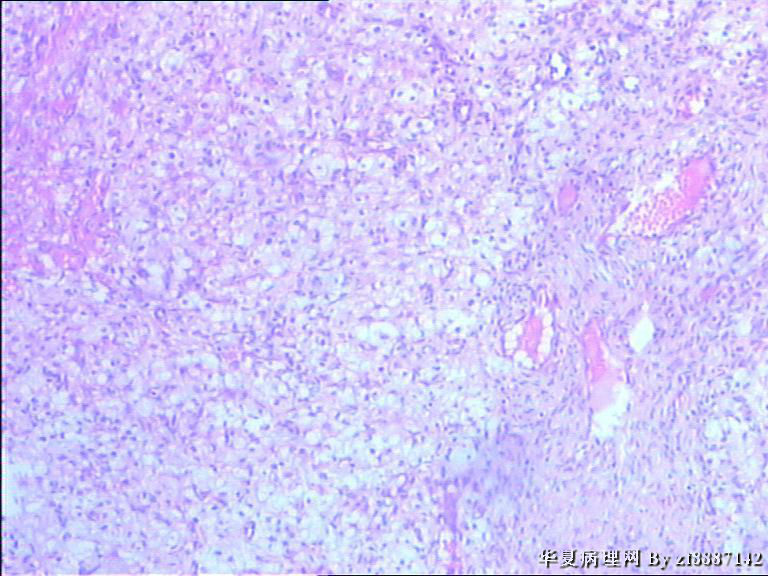

卵巢囊性肿块约3cm*3cm*3cm,表面光滑,包膜完整,内有清量液体,壁厚约0.3,

大量上看起有点向黄体,但镜下为什么胞浆这么空亮,这是什么。